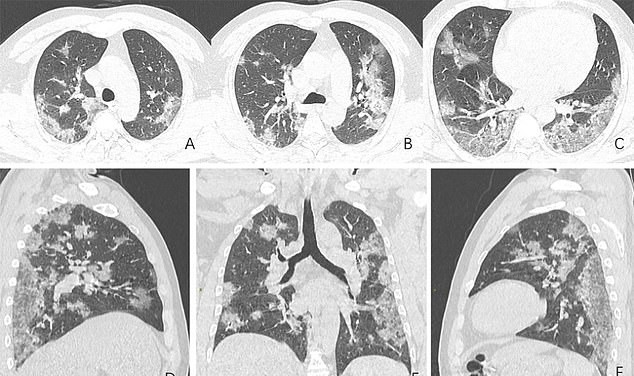

Scans show white patches in the lower areas of the lungs. Radiologists indicate those white patches ground glass opacity, a partial filling of air spaces.

Released by the Radiological Society of North America, the scans show how the fluid in the spaces became more noticeable over time. The patient was hospitalized on December 25, 2019, after experiencing cough and a fever for almost two weeks.

He was diagnosed with acute respiratory distress syndrome and pneumonia. Despite receiving treatment, he passed away one week later.